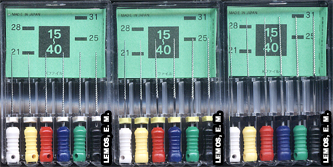

Entretanto, eles também são divididos por séries - diâmetro do D1, sendo a série especial #06 (cor rosa), #08 (cor cinza) e #10 (cor roxa), primeira série de #15 a #40, segunda série de #45 a 80 e terceira série de #90 a #140. Há também uma seqüência de cores, iguais para primeira, segunda e terceira séries: branca, amarela, vermelha, azul, verde e preta. Importante salientar que, os instrumentos #06 e terceira série, normalmente não são solicitados no Curso de Graduação. |

Tipo K Série Especial 25mm #06, #08 e #10 |

Tipo K 1a. Série 25mm #15 ~ #40 |

Tipo K 2a. Série 25mm #45 ~ #80 |

Tipo K 3a. Série 25mm #90 ~ #140 |

Além dos diâmetros citados acima, todos instrumentos podem variar de comprimento, sendo: 21, 25 e 31mm, dependo não somente do diâmetro, mas também do comprimento do dente a ser tratado endodônticamente. |